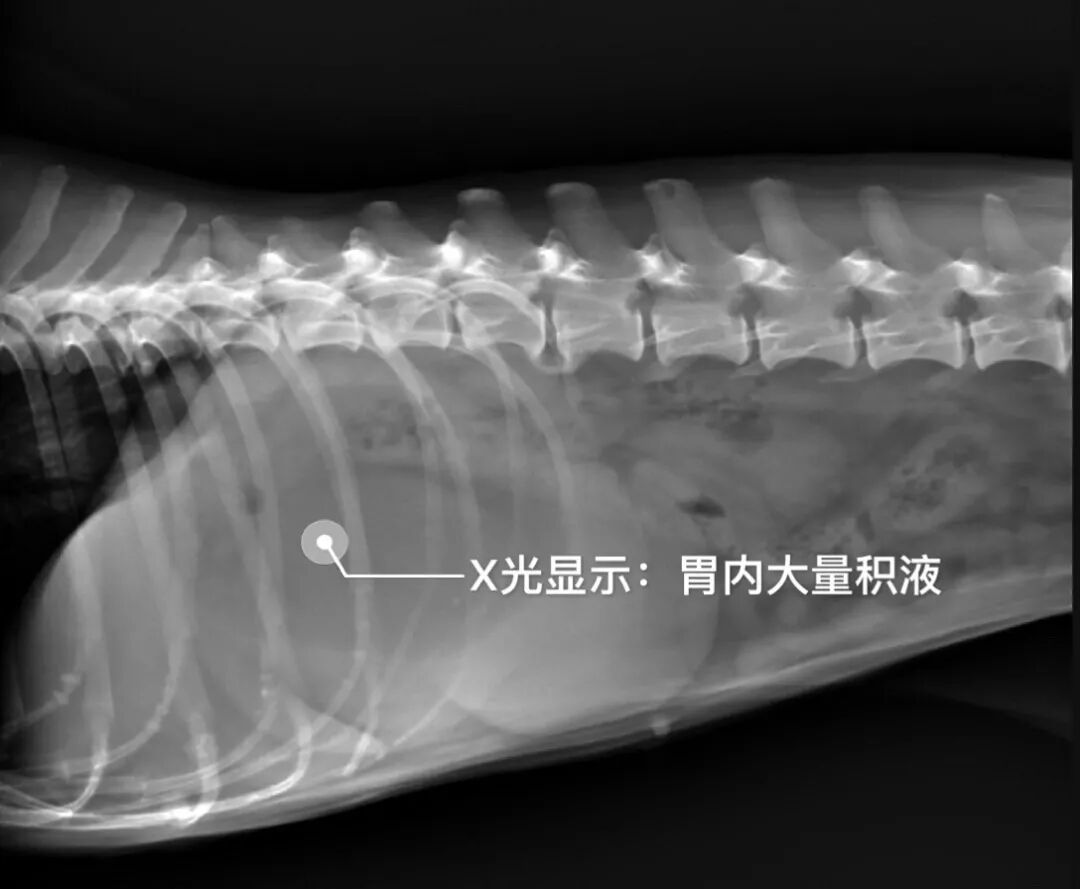

▲DR(数字X线摄片)检查

DR及B超检查结果显示:阿呆胃扩张,内部有大量积液,以及十二指肠部位有肿块,医生初步诊断为堵塞性呕吐。